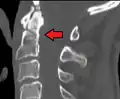

A fracture of the base of the dens as seen on plain X-ray -

A fracture of the base of the dens as seen on CT -